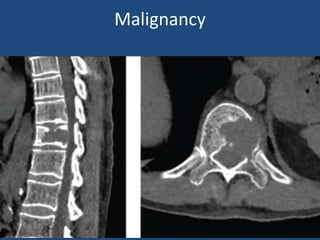

Malignancy

Tumors